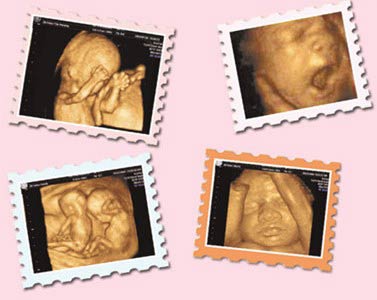

西安安琪儿妇产医院引进动态彩超系统(4D),能够清晰显示出未出生宝宝的即时动态活动图像,可以将宝宝的样子和动作制作成照片或影响光盘,让他拥有更完整的零岁相册,给父母及今后的孩子留下珍贵的纪念。更为重要的是,四维彩超能够全方位、多角度的观察宫内胎儿的生长发育情况,为早期诊断胎儿先天性体表畸形和先天性心脏疾病提供了准确全面的科学依据。

5.深刻意义:通过四维彩超,准妈妈可以清楚的看到宝宝的模样和宝宝的动作,为宝宝制作“零”岁相册,甚至可以刻录成光盘,有重大的纪念意义。